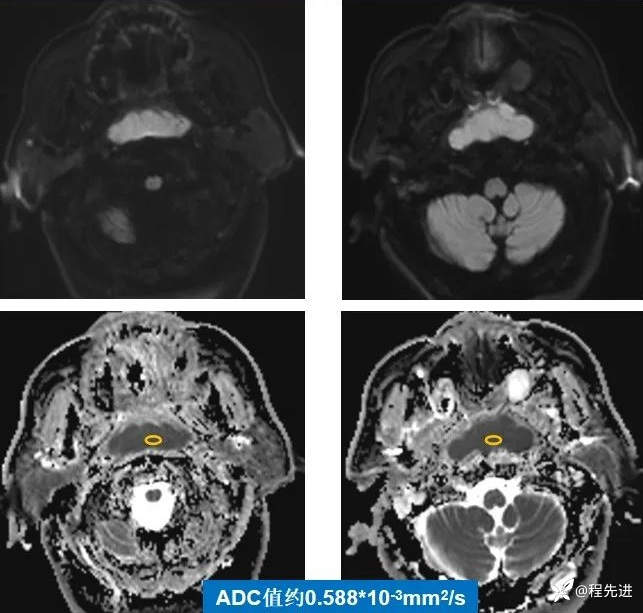

DWI、ADC: